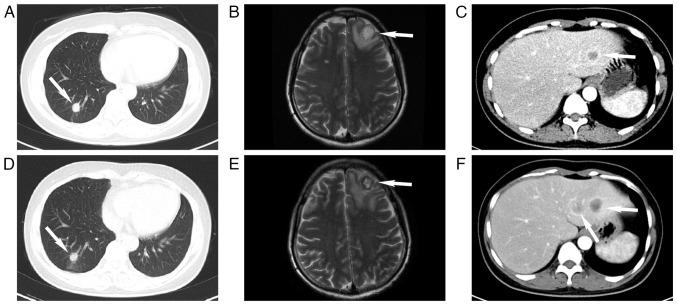

Pulmonary adenocarcinoma with breast metastasis is rarely encountered in clinical practice. Therefore, precise clinical diagnosis of patients with this disease is crucial when selecting subsequent treatment modalities and for overall prognosis assessment. The present study reported on a case of lung cancer with breast metastasis harboring the fusion. The patient was initially diagnosed with triple-negative breast cancer with lung metastasis, but comprehensive breast cancer treatment was ineffective. Reevaluation of the patient's condition via lung biopsy revealed primary lung adenocarcinoma. In addition, the results of genetic testing revealed the fusion protein in both lung and breast tissues. After treatment with inhibitors, the patient's symptoms improved rapidly. This case highlights the prolonged diagnostic journey from presentation with a breast mass to ultimately being diagnosed with lung cancer with breast metastasis, underscoring the critical need for heightened awareness among clinicians regarding the possibility of rare metastatic patterns. Timely identification of lung cancer with breast metastasis, facilitated by comprehensive genetic testing, not only refines treatment decisions but also emphasizes the importance of interdisciplinary collaboration in navigating complex clinical scenarios. Such insight contributes to the ongoing development of personalized cancer care that guides clinicians toward more effective and tailored therapeutic strategies for patients with similar diagnostic challenges.

肺腺癌伴乳腺转移在临床实践中很少见。因此,对于患有这种疾病的患者,准确的临床诊断对于选择后续治疗方式和评估总体预后至关重要。本研究报告了一例伴有 融合的肺癌伴乳腺转移病例。该患者最初被诊断为三阴性乳腺癌伴肺转移,但综合乳腺癌治疗无效。通过肺活检对患者病情进行重新评估后发现原发性肺腺癌。此外,基因检测结果显示肺和乳腺组织中均存在 融合蛋白。在用 抑制剂治疗后,患者症状迅速改善。该病例凸显了从出现乳腺肿块到最终被诊断为肺癌伴乳腺转移这一漫长的诊断过程,强调临床医生迫切需要提高对罕见转移模式可能性的认识。通过全面的基因检测及时识别肺癌伴乳腺转移,不仅能优化治疗决策,还强调了跨学科协作在应对复杂临床情况中的重要性。这种见解有助于推动个性化癌症护理的持续发展,指导临床医生为面临类似诊断挑战的患者制定更有效、更具针对性的治疗策略。